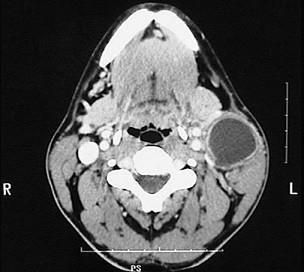

问题 图示是鳃裂囊肿患者的CT 检查结果,关于此病的描述错误的是 ( )

选项 A.可形成瘘 B.可继发感染 C.大小不定,生长缓慢 D.无自觉症状 E.触之有搏动感

答案 E